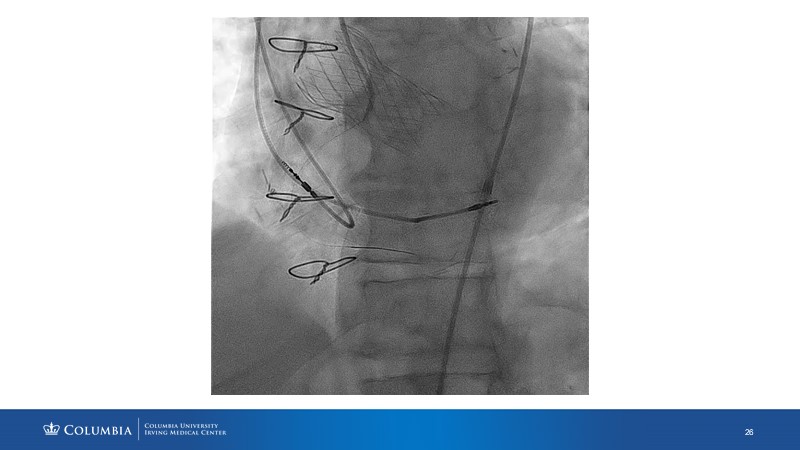

Through the presentation of real-life clinical cases, this session will allow you to discover the use of ALLEGRA for valve-in-valve TAVI, understand the management of coronary artery disease in TAVI patients, better detect when and how to protect coronary arteries during TAVI, or even learn how to perform commissural alignment with ALLEGRA.

- To better detect when and how to protect the coronary arteries during TAVI